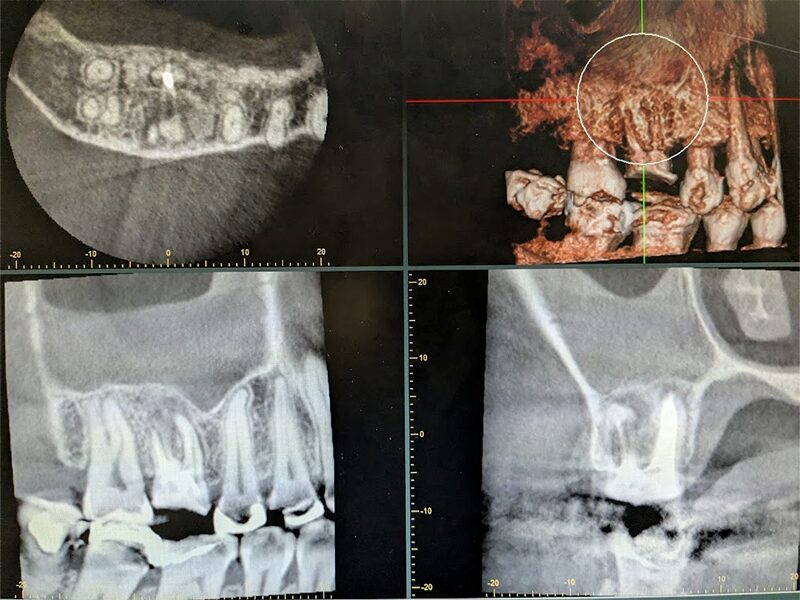

根管治療の再治療になりますが、歯根が弯曲・閉塞しているため根管治療で病巣が治癒せず、上顎洞粘膜の肥厚も残っております。

術後3か月のCT経過写真です。まだ上顎洞炎は残っています。